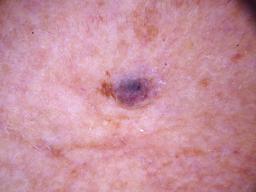

Training set from the ISIC 2018 Challenge.

[1] Noel Codella, Veronica Rotemberg, Philipp Tschandl, M. Emre Celebi, Stephen Dusza, David Gutman, Brian Helba, Aadi Kalloo, Konstantinos Liopyris, Michael Marchetti, Harald Kittler, Allan Halpern: "Skin Lesion Analysis Toward Melanoma Detection 2018: A Challenge Hosted by the International Skin Imaging Collaboration (ISIC)", 2018; arxiv.org/abs/1902.03368

[2] Tschandl, P., Rosendahl, C. & Kittler, H. The HAM10000 dataset, a large collection of multi-source dermatoscopic images of common pigmented skin lesions. Sci. Data 5, 180161 doi:10.1038/sdata.2018.161 (2018).